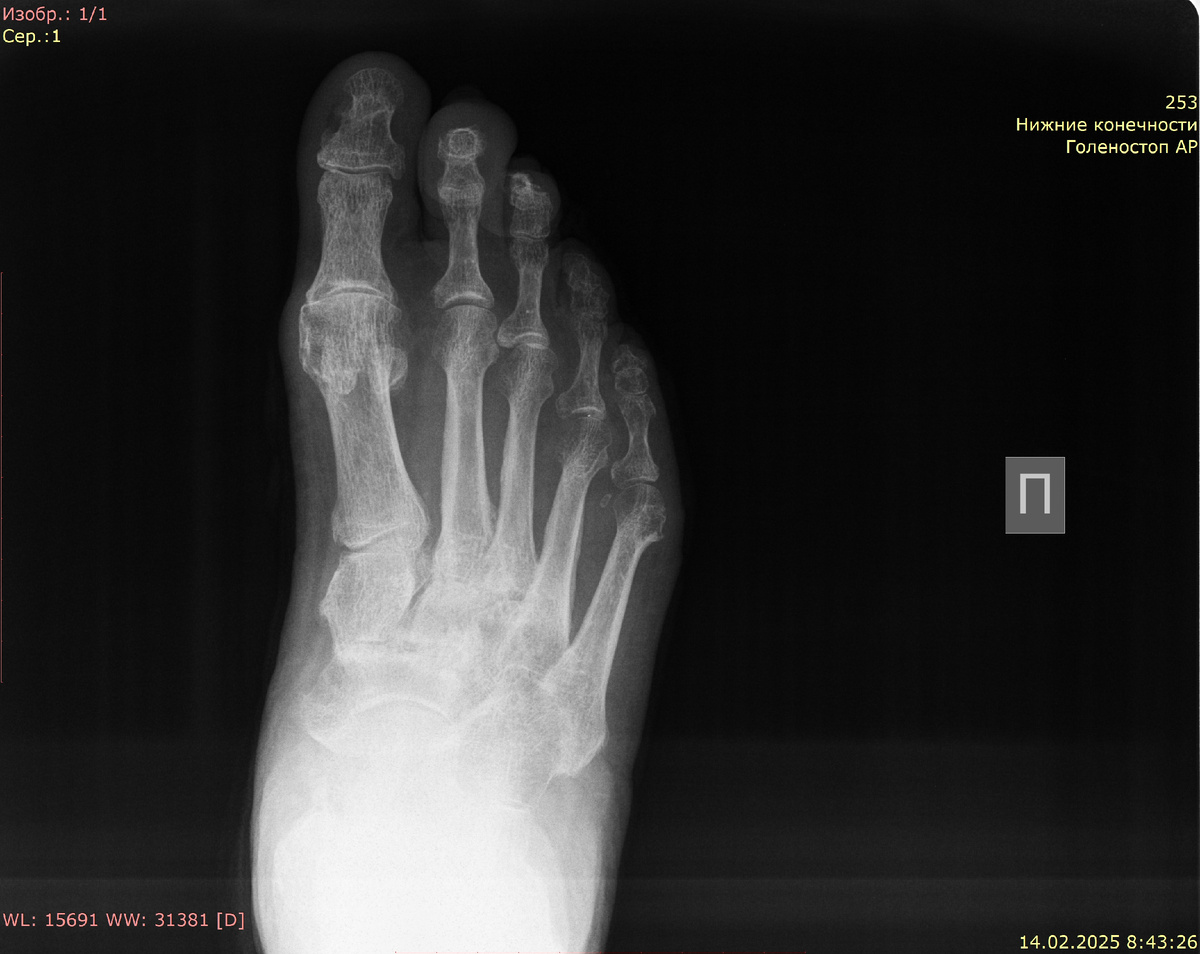

Рентгенография правой стопы в прямой и косой проекциях:

Аномалий развития не выявлено. Форма, размеры и структура костей стопы не изменены. Просветы суставных щелей в суставах стопы неравномерно сужены. Суставные поверхности уплотнены, в субхондральном слое остеосклероз. Оссификаты по краю суставных поверхностей. Костно-травматических и костно-деструктивных изменений не выявлено. Мягкие ткани без патологических рентгенопозитивных включений.

Заключение: артроз суставов правой стопы II-III степени по Келлгрену-Лоуренсу. Костно-травматических изменений не выявлено